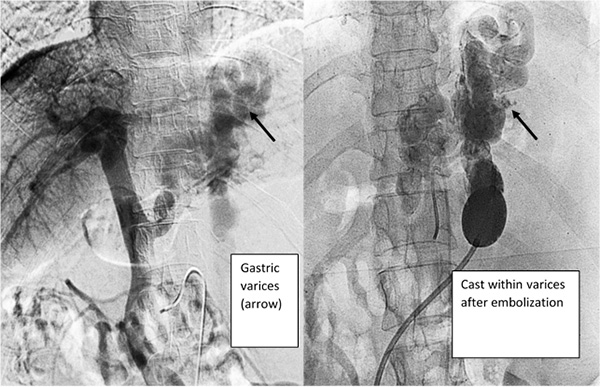

We will then perform a venography, which is a type of imaging technique in which X-rays are used to see the vessels clearly. This will allow us to confirm exactly which vessels need to be treated and if there are any other abnormal or dilated vessels which have not previously been identified. A medication will then be injected into the dilated abnormal venous channels through the catheter, until they are completely filled. Finally, the balloon will be deflated and we withdraw the catheter in cases of BRTO and in cases of PARTO Vascular Plug is permanently deployed in the shunt.

Recent reports have stated that BRTO/PARTO is a less invasive and more effective way to manage gastric varices than shunt surgery or TIPS. BRTO/PARTO can in most cases completely obliterate these abnormal bleeding venous channels. One of the greatest advantages of BRTO is its preservation of liver function. Moreover, the increase of blood flow in BRTO can also improve liver function in cases where the patient has cirrhosis (scarring of the liver).